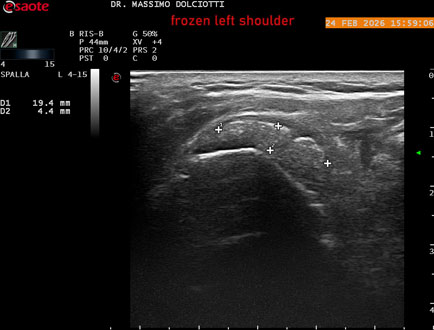

Data inserimento: 02/03/2026

Ecografia del: 24/02/2026

Strumento: Esaote MyLab Eight

Sonda: Lineare Multifrequenza 4-15 MHz

Età Paziente: F 71 anni

Motivazione dell'esame: da 1 mese dolore alla spalla sinistra, anche di notte.

Commento all'esame: le immagini ed il video documentano il tendine sovraspinato sinistro spiccatamente disomogeneo, per presenza di immagine iperecogena, delle dimensioni di 21 x 4 mm, da ricondurre a estesa calcificazione. Quadro clinico di spalla congelata.

Conclusioni: spalla sinistra congelata (frozen left shoulder).